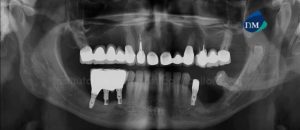

Paciente femenino de 29 años de edad, es referido al Instituto de Diagnóstico Maxilofacial – IDM (Sede Miraflores) para examen tomográfico con motivo de colocación